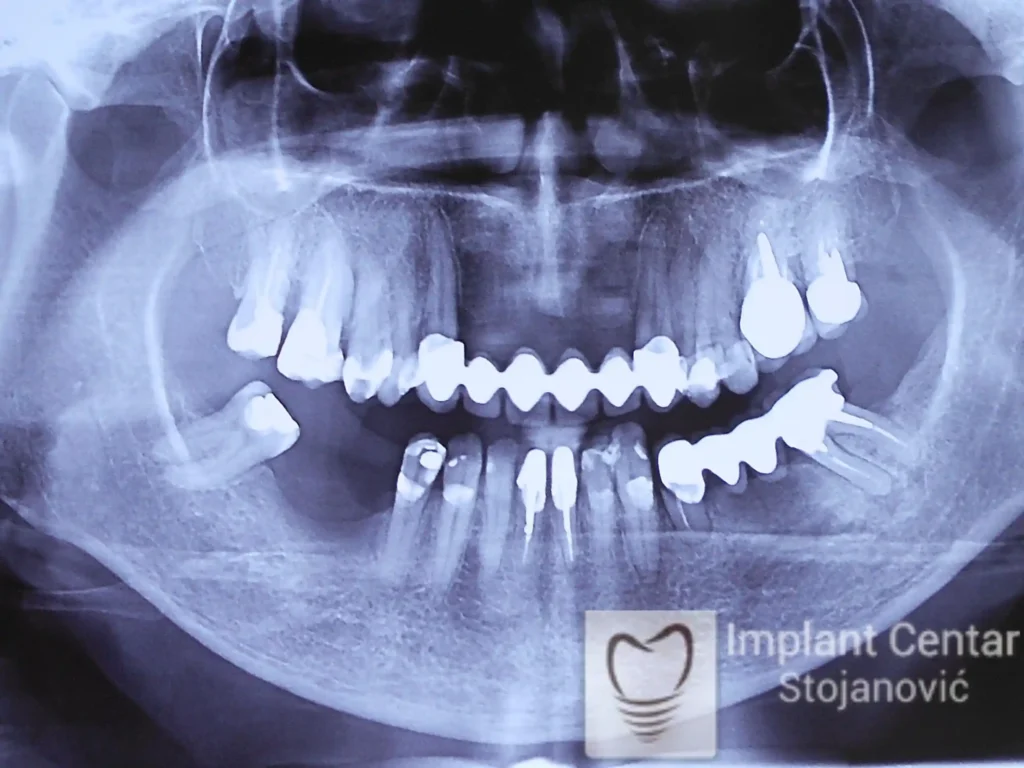

Na slici 1. slici 2. vidi se početno stanje — pacijent je imao prirodne zube, ali samo izradom novih mostova nije bilo moguće postići normalan odnos gornjih i donjih zuba (eugnatan zagrižaj).

Zbog toga je plan terapije uključivao vađenje svih preostalih zuba i ugradnju implantata u gornjoj i donjoj vilici. U gornjoj vilici postavljena su i dva tuberopterigoidna implantata, kao zamena za sinus lift proceduru, što se može videti na ortopan snimku nurađenom odmah nakon ugradnje (slika 3).